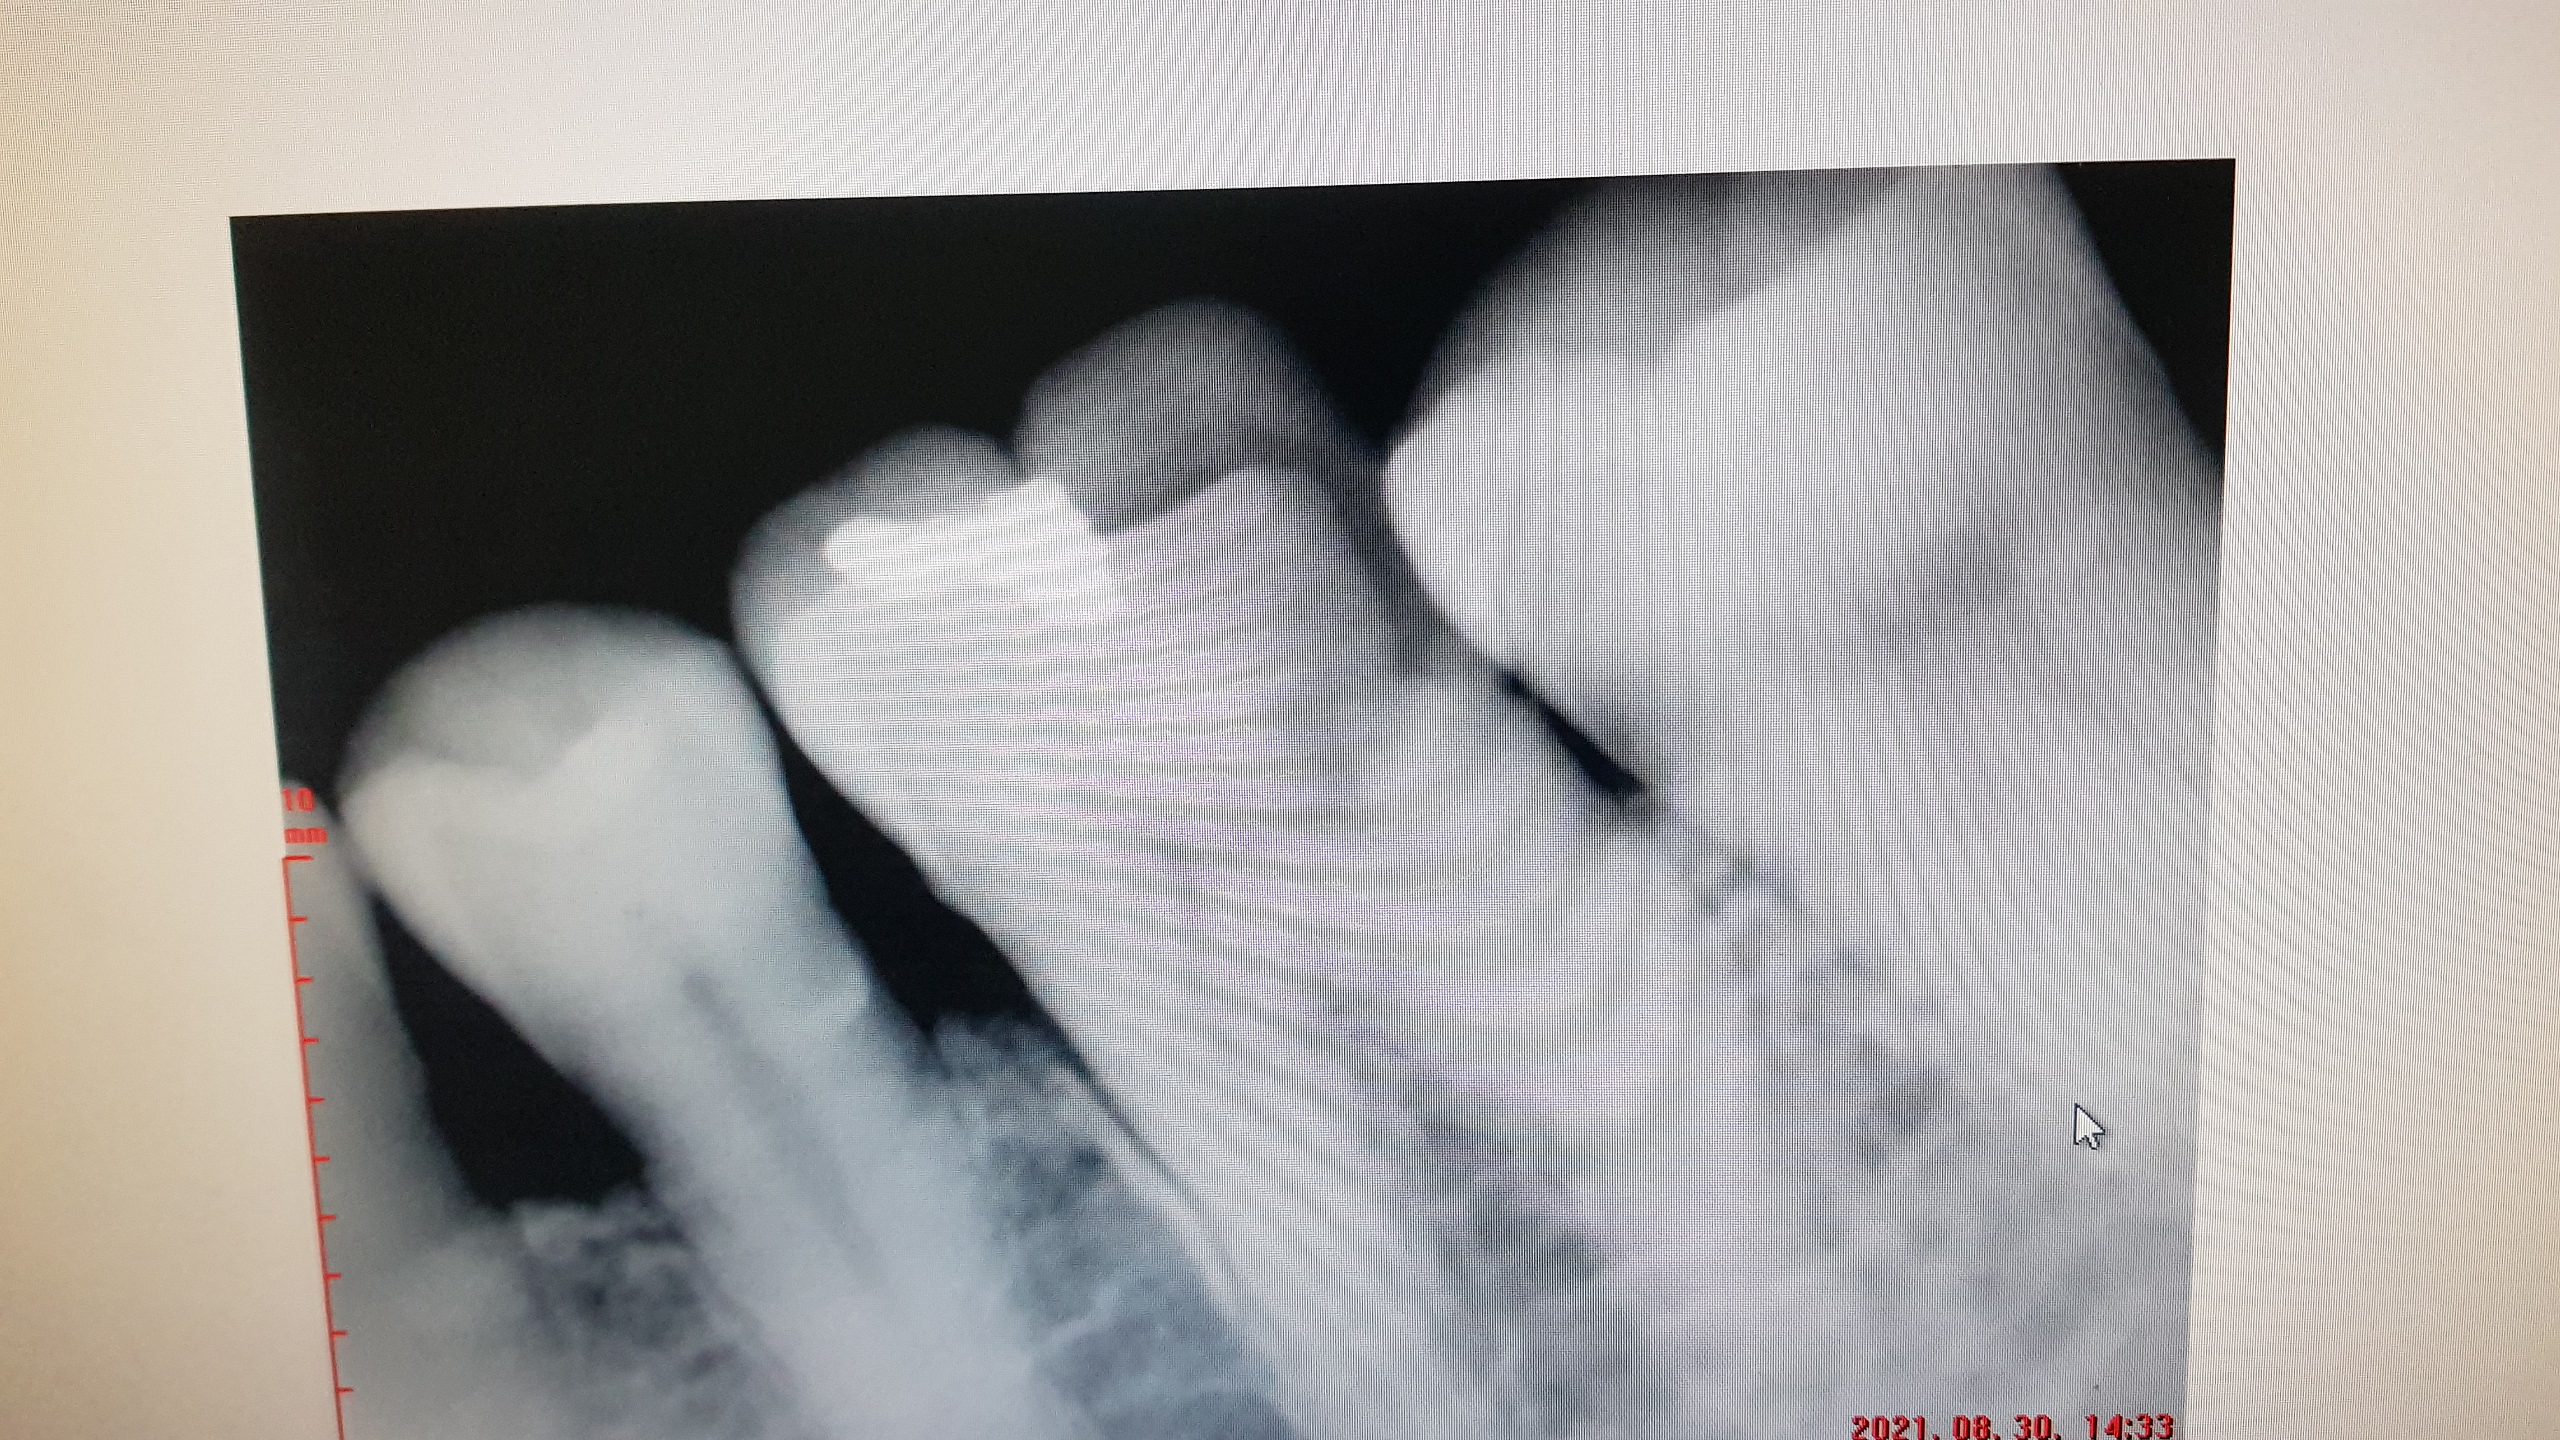

엑스레이를 찍었다..

치료가 잘되었다고..설명해 줍니다..

그리고 실제 내 입속의 치아 사진..

더러울수도 있으니...잠간 고민을 하고 ..보든지 말든지..